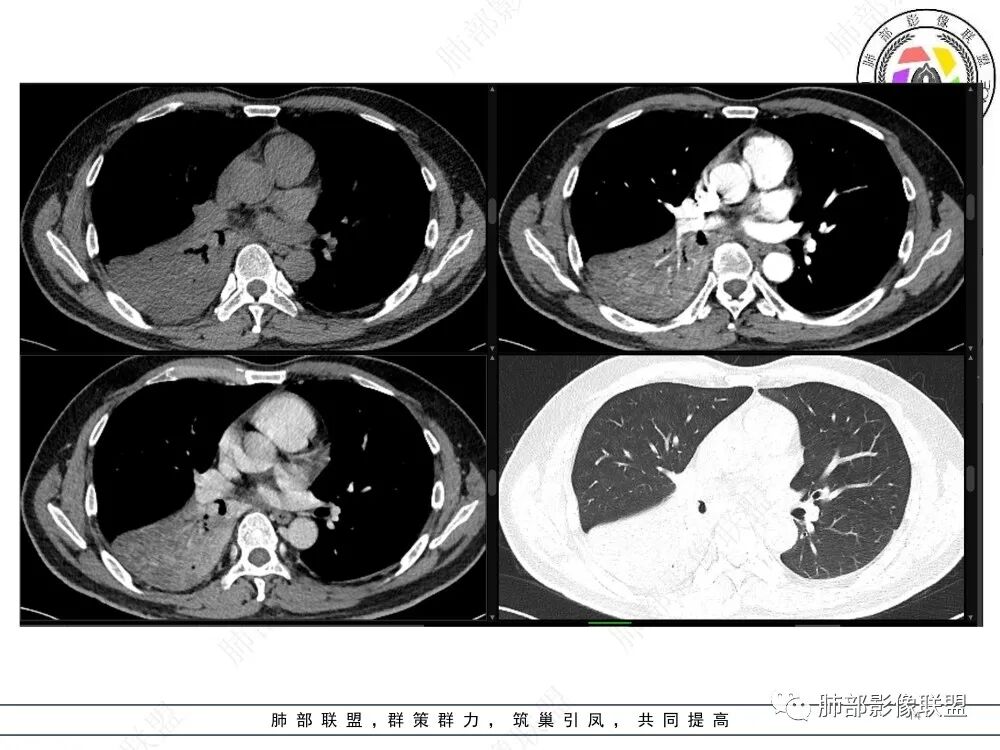

右肺下叶实变,周围磨玻璃,近端支气管扩张,管壁凹凸不平,远端阻塞,可见粘液栓,不均匀强化,有低密度无强化影,其内血管显示尚可,考虑粘液腺癌,鉴别淋巴瘤

右肺下叶大片实变,密度不均匀,可见支气管充气征及粘液区,右肺下叶支气管内结节影,下叶支气管阻塞,病灶前下可见磨玻璃影,右侧积液,考虑粘液腺癌,鉴别类癌?

右下叶支气管狹窄,内见高密度强化结节,远端大片不张实变,实变内可见多发粘液拴,整体观察实变似有见缝就针的感觉,综和分析考虑粘液表皮样癌,其次考虑类癌

右肺下叶支气管见结节灶继发右肺下叶膨胀不全,右肺中央局部炎性改变,下叶支气管结节动脉期明星强化,静脉期强化减低,首先考虑肺鳞癌,鉴别类癌、粘液表皮样癌。

首先血管未见明显侵犯、移位,提示病灶:炎性;肿瘤:外朝内——含粘液类腺癌(肺门淋巴结转移),腔内肿瘤(鳞癌、腺癌、类癌、小细胞、粘液表皮等)

从强化看:外周密度低,强化弱

就不太符合腔内肿瘤远端不张的表现,因为外围不张——强化明显

这一例反了

按这个特点周围要考虑肿瘤组织

腔内肿瘤,远端堵塞

这个外面明显也是肿瘤部分

可能含有粘液所以这么低